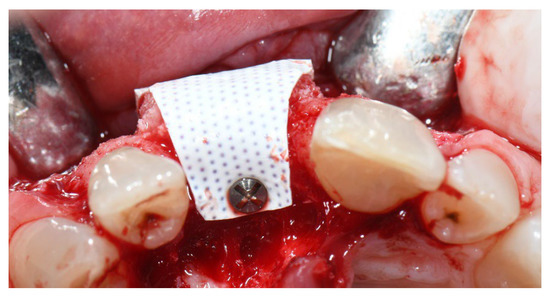

2.2. Clinical Procedures

3. Results